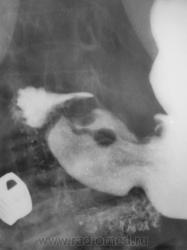

1. Аденоидные полипы в антральном отд. желудка.

2. Варикозно расширенные вены пищевода.

Во всяком случае полиповидное выпячивание в антруме налицо, но думаю оно подслизистое... А варикоз - явно не виден, есть в кардии складка небольших размеров, но явно в глаза она не бросается, хотя складки везде толстоваты...

полиповидные образования в антральном отделе +грыжа ПОД

Смею предположить (с учетом наличия + тени кардии желудка по верхне-медиальной стенке, некоторого удлинения и выпрямления кардиального канала, неровности контуров) кардио-эзофагеальный рак без стеноза. В антруме - полипы. Вряд ли подслизистые образования, такие на вершине складок не образуются.

На снимке который поместил Анатолий Владимирович, м.б. или ГПОД (кардиальная) или ахалазия пищевода,при ней газовый пузырь отсутствует или уменьшен в размере. А м.б. и c-r пищеводно-желудочного перехода.

Мне вообще микрогастрия видится, по крайней мере, опухоль в обл. свода желудка инфильтративная (что нетипично для свода).

Наблюдение архивное. Я этот снимок привел как типичный пример ампулы пищевода, нормальной, в горизонтальном положении тела, которую наша братия, почти поголовно принимает за грыжу пищеводного отверстия, и соответственно с нашей подачи хирурги пытаются это оперировать...

1.о варикозе вен н\трети пищевода стоит подумать, весьма коварная вещь;

2. полипы препилорического отдела не вызывают сомнения, но что тут интересно - картинка то меняется, периодически крупный дефект выполнения как бы исчезает...но появляется в основании луковицы - сдается мне - это полип на длинной ножке, вот и гуляет он через привратник туда-сюда, вспоминайте - симптом "собачки на цепочке"...

3. опухоль кардиального отдела сомнительна...и весьма

Да, данные ФГДС подтвердили наличие полипов в препилорической части, один действительно - "гулящий" - на длинной ножке.